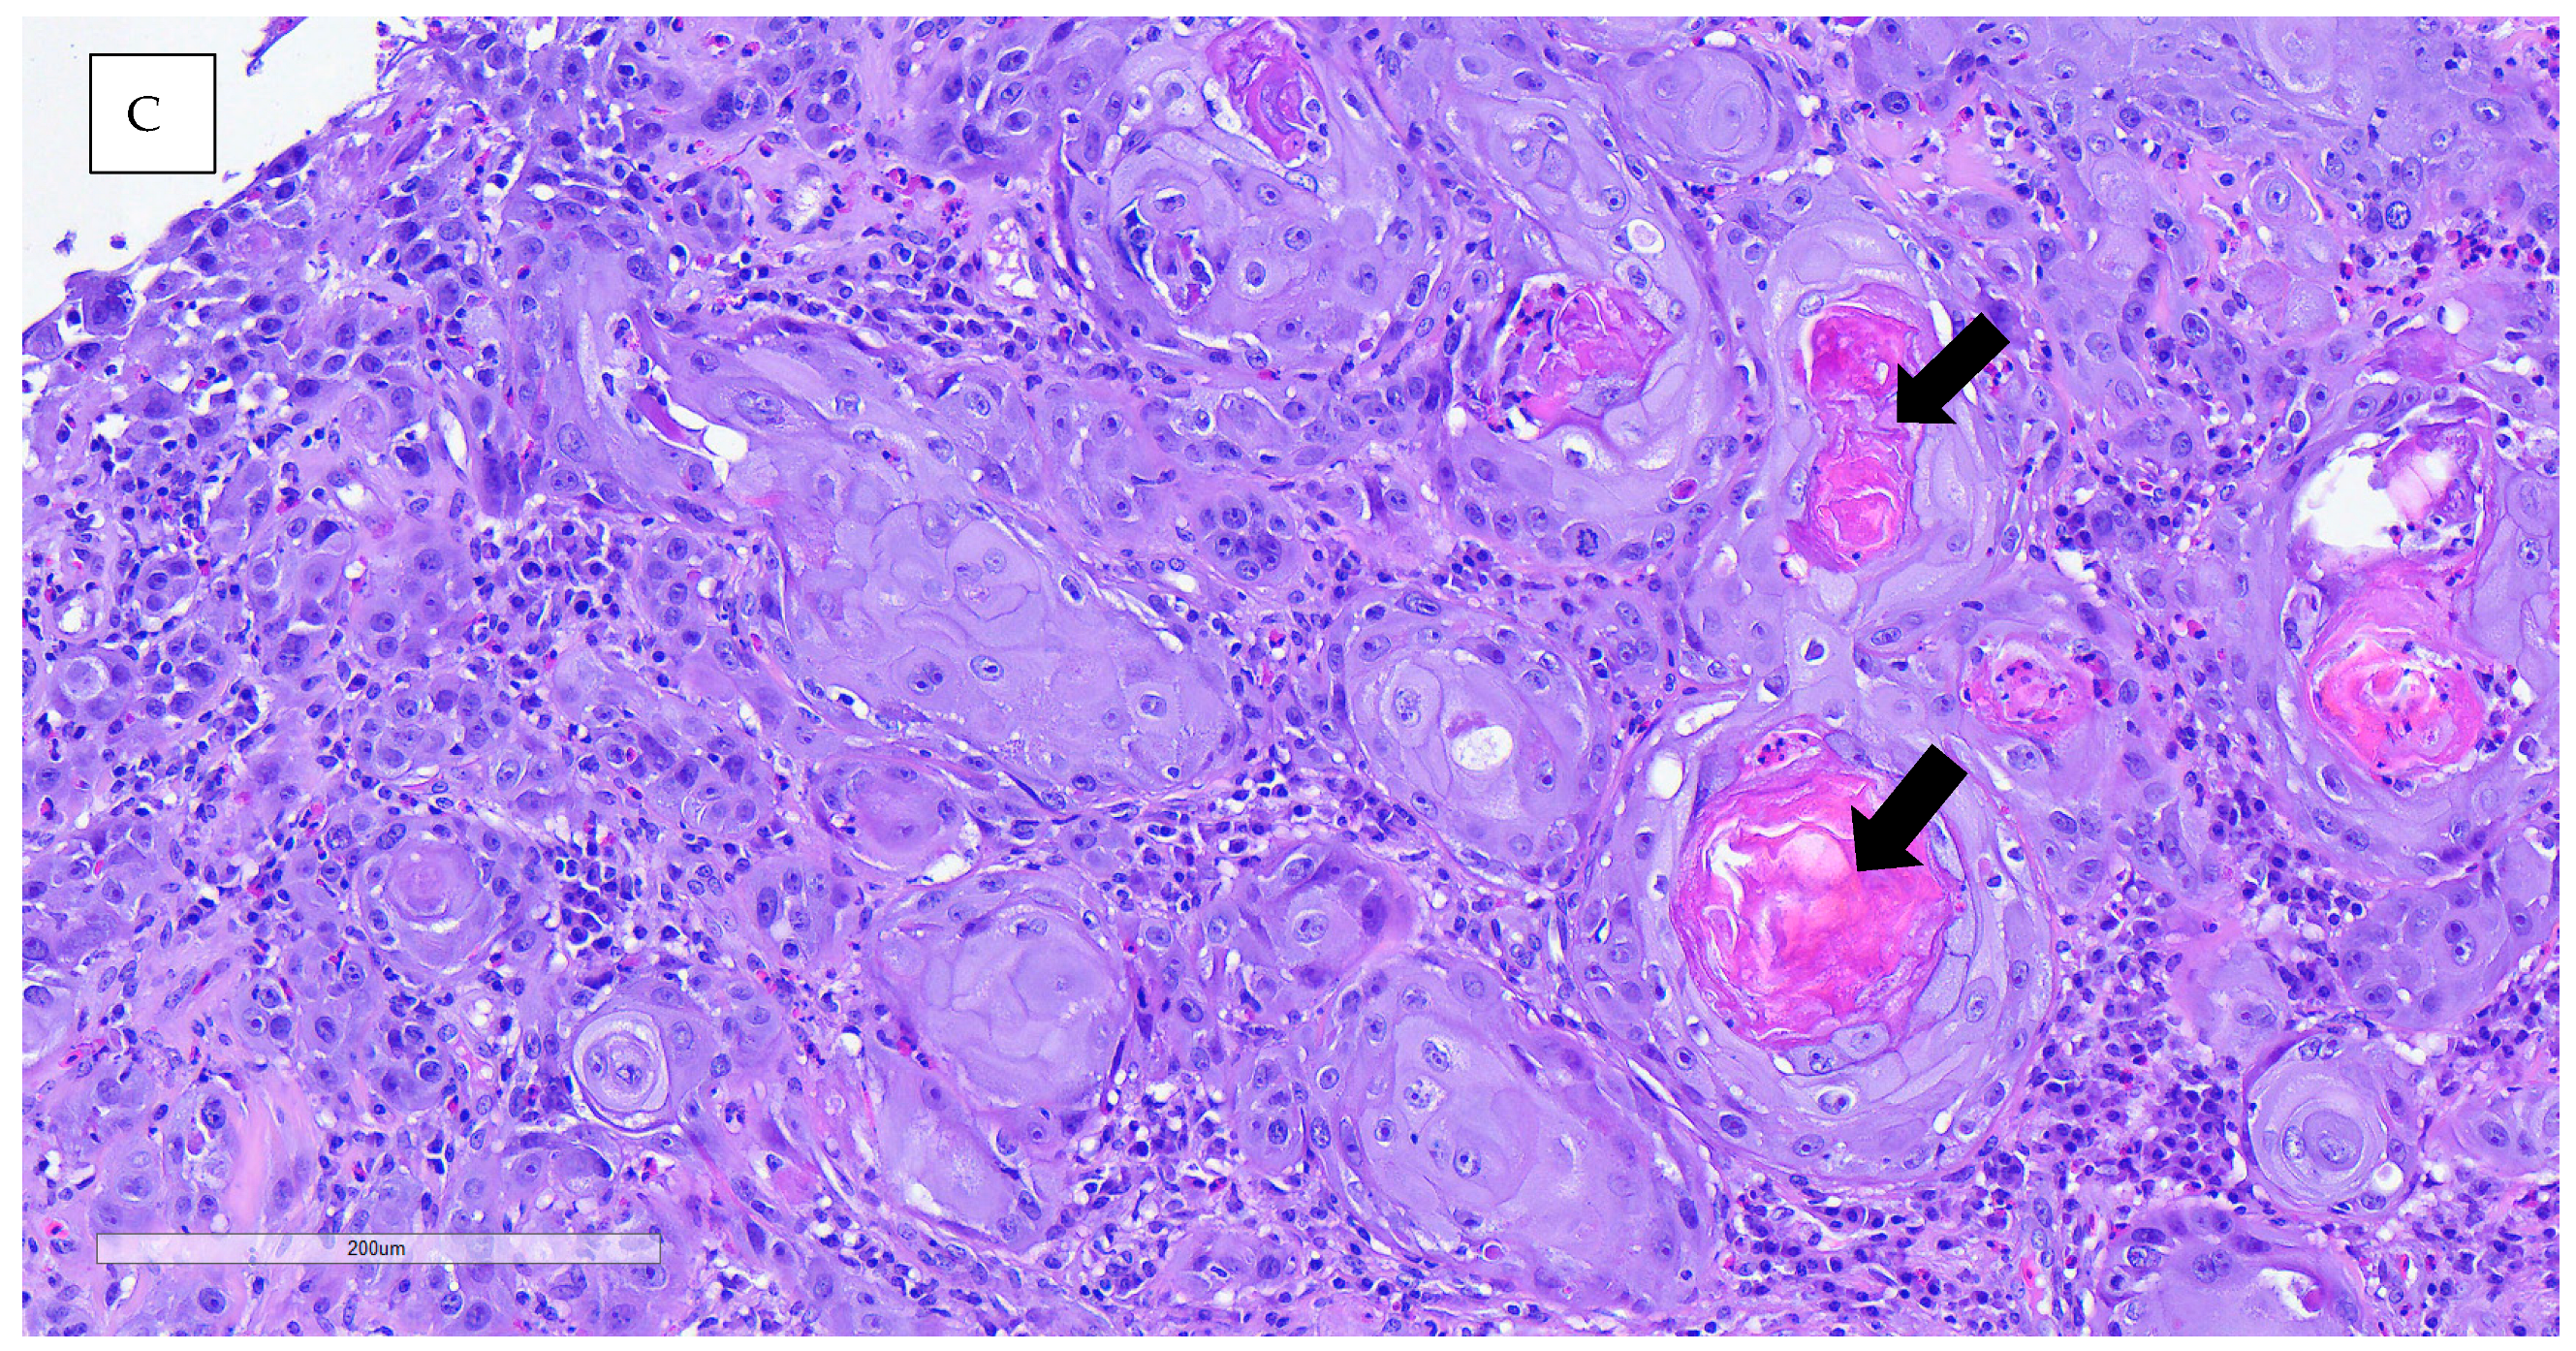

An incisional biopsy was performed in order to obtain further information. Anesthesia was conducted via inhalation of isoflurane. The biopsy was processed routinely with paraffin-embedded tissue and hematoxylin–eosin (H&E) stain for histopathological study. Histopathological analysis revealed neoplastic proliferation, characterized by nonencapsulated, poorly demarcated, and infiltrative growth, which effaces and replaces the epidermis and dermis, reaching the surgical margins. The neoplasm was arranged in nests of multiple layers with squamous differentiation (keratin pearls), surrounded by desmoplastic mature connective tissue. The neoplastic cells were polygonal, with abundant eosinophilic cytoplasm and partially defined cellular borders. One or more nuclei were present, round to oval in shape, with stippled chromatin. The anisocytosis and anisokaryosis rates were high, and the mitotic count was moderate. Other microscopic findings included severe epidermal ulceration replaced by serocellular crusts, peripheral epidermal hyperplasia with hyperkeratotic orthokeratosis, and severe interstitial inflammatory infiltrate mainly composed of heterophils, lymphocytes, and plasma cells. The definitive diagnosis for both lesions was invasive squamous cell carcinoma, accompanied by ulcerative and heterophilic dermatitis. The nature of the dermatitis was determined to be subacute to chronic, with the presence of bacterial contamination (Figure 5).

Figure 5.

(A) The microscopic images showed orthokeratotic and epithelial neoplastic proliferation, not encapsulated or well delimited and infiltrative. Intense hyperkeratosis is observed in the non-ulcerated epidermis. (B,C) Neoplastic cells growing, forming nests of multiple layers with scaly differentiation, with some pearls of keratin observed. They are surrounded by an abundant amount of mature fibrous tissue interstitial (intense fibrous desmoplasia). The neoplastic cells are polygonal, with abundant eosinophilic cytoplasm and well-defined cytoplasmic borders.